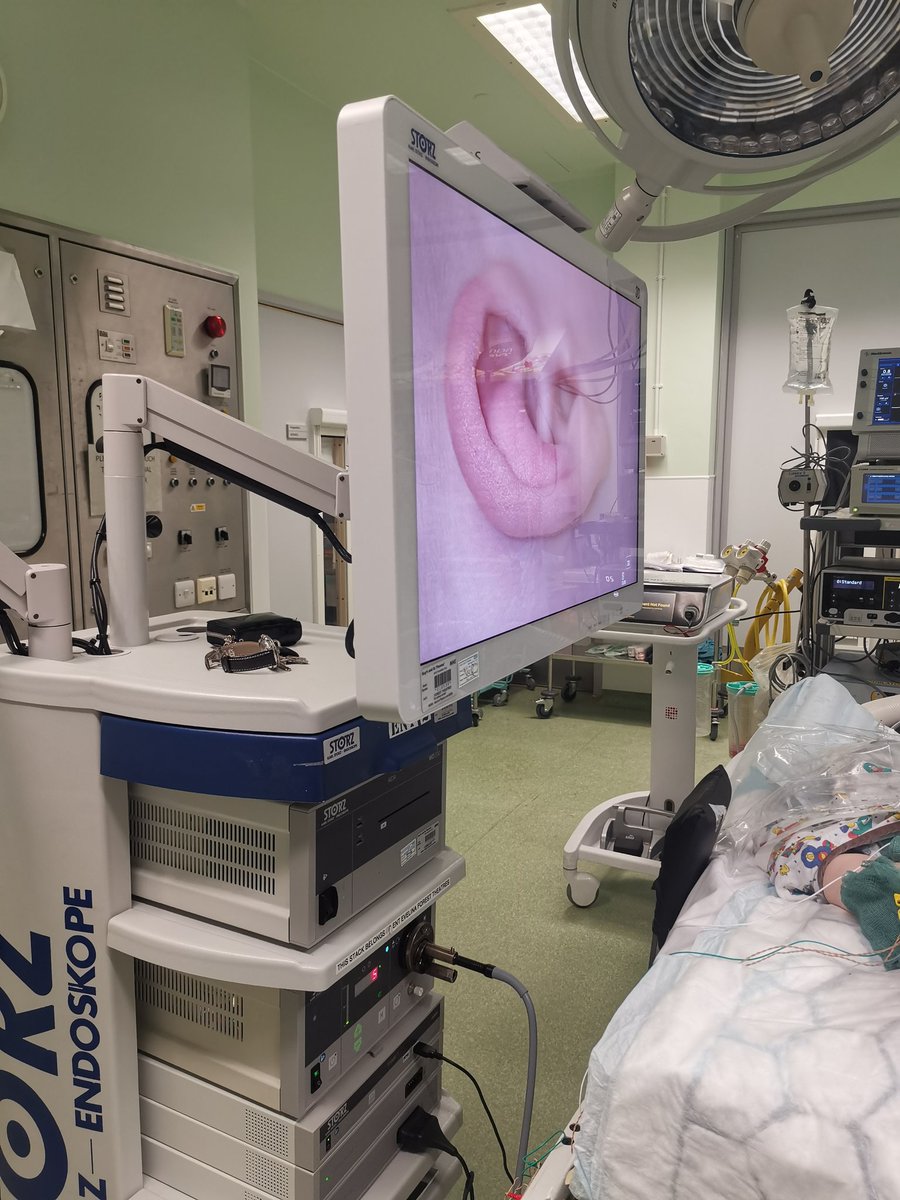

Not head down, head up! Cochlear implant with exoscope, a great tool to transform surgeon's experience..Evelina London